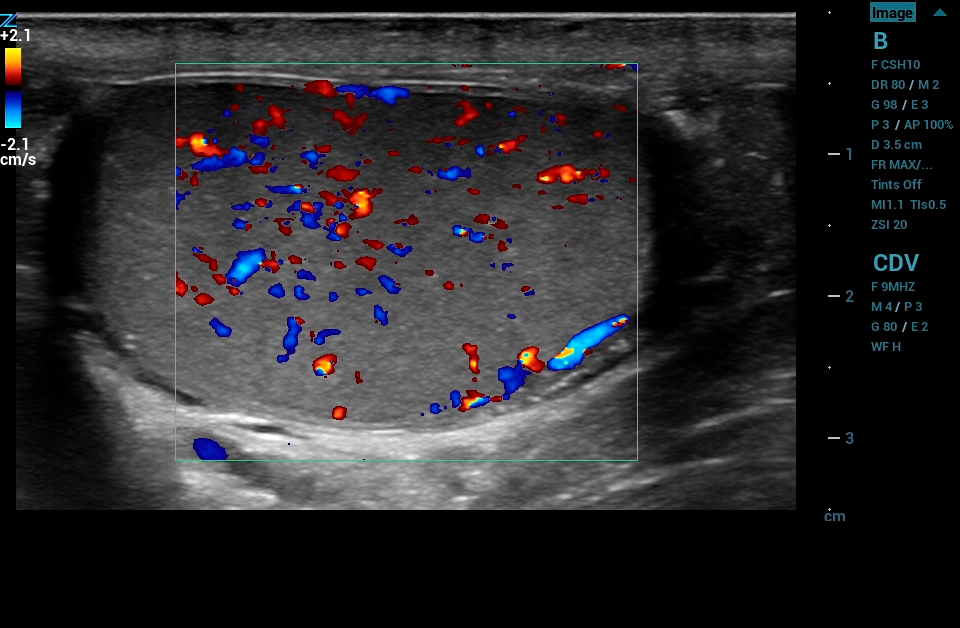

ARFI

ARFI Elastography* with quantification is a non-invasive method of assessing liver tissue stiffness. Using real time imaging as a guide, ARFI automatically calculates liver tissue stiffness values (AVG, MEAN, and IQR) for a predetermined region of interest. Multiple samples can be recorded and displayed in a report.

* Available on the C4-1 transducer

Contrast Enhanced Ultrasound (CEUS), Mindray’s unique approach to contrast imaging, allows clinicians to obtain the information needed with a lower dose of the contrast agent. CEUS is now available on all imaging transducers (1-20MHz).